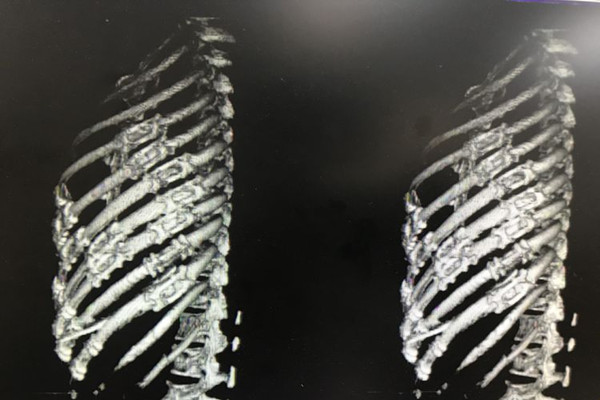

患者李某,在工作时不慎被搅拌机绞压胸腹部及左上肢,急诊转入我院时,颜面部青紫,上半身遍布出血点,左侧胸廓塌陷,反常呼吸明显,右侧呼吸音明显减弱,腹部压痛明显,左上肢严重毁损,情况十分危急。急诊科医护人员立即开通绿色通道,快速完成CT检查,实施紧急救治,并通知胸心外科和麻醉科及辅助科室做好抢救准备。结果提示,患者左侧多根多处肋骨骨折、左侧胸腔积液、右侧膈疝、脾脏破裂,肝脏挫伤,左上肢粉碎性骨折。

患者胸腹部挤压伤并创伤性窒息,病情极其危重,随时都会有生命危险,容不得半点耽搁。在对患者病情与手术方案进行细致的讨论后,由我院胸外科、创伤骨科、普外科、手麻科等科室专家组成的医疗团队立即对患者进行急诊手术抢救。胸外组经胸腔镜辅助行双侧胸腔探查见左侧4-12肋骨骨折,其中4-10肋骨成粉碎性骨折,左肺下叶广泛挫裂伤,胸腔积血2000余毫升,双侧膈肌破裂、肝脏完全疝入右侧胸腔。普外组探查腹腔积血1000余毫升、脾脏破裂。创伤骨科组探查见左上肢粉碎性骨折,软组织毁损严重,在多学科协作下成功完成左侧血胸清除、肺修补、左侧膈肌修补、左侧肋骨骨折复位内固定术等手术。各学科争分夺秒,配合默契,凭借着娴熟的医疗技术和丰富的临床经验,让奄奄一息的患者重获新生。